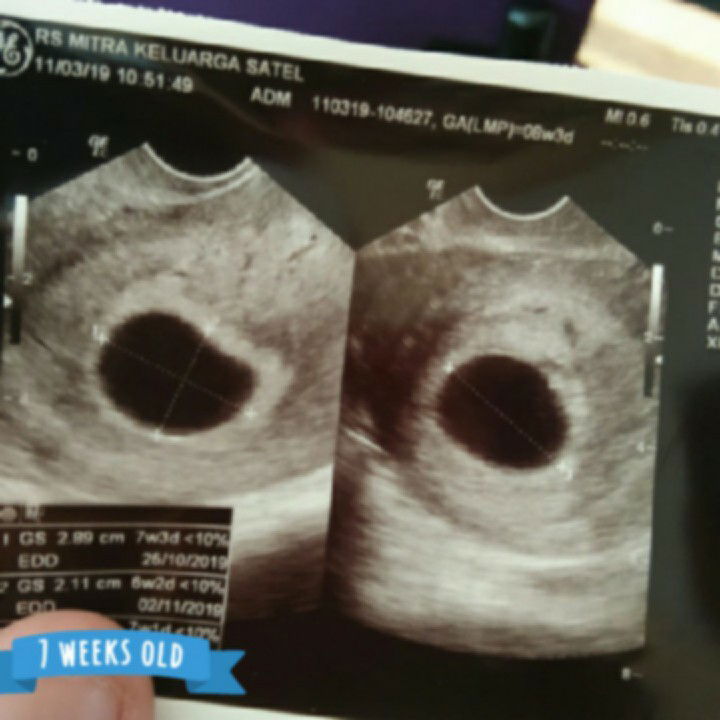

Hallo, Bunda. Ini postinganku tanggal, 11 Maret 2019 dengan sedikit tambahan karena pulang kantor suamiku meluk aku sambil nangis. Makasih ya, Bunda-Mommies yang udah komen2 kemarin. Mohon bagi semangat lagi, ya. Aku baru nikah Desember kemarin. Hari pertama mens terakhir 11 Januari lalu. Seneng karena hamil. Ga lama lagi akan jadi orang tua. Tapi, hari ini sedih, Bund. (btw, itu tgl 11 Maret). Perdana cek kandungan di dokter kandungan, di usia 7 minggu 3 hari lewat USG abdomen sama transvaginal. Dokter bilang ga ada janin yang terlihat di kantung rahimku. Kantungnya kosong. Biasanya, usia 7 minggu itu udah ada janin yang keliatan. Ini ga keliatan apa-apa. Gelap semua. Diagnosis pertama katanya BO alias hamil kosong. Nanti aku posting fotonya, Bund. Sedih super duper stres. Padahal, ga ada flek dari awal telat mens. Sempet bilang kram perut dikit. Dokter bilang itu mau kontraksi keguguran. Kalau tiba-tiba pendarahan langsung ke UGD aja. Tapi, baca-baca, kram pada orang hamil itu biasa. Dokter ga ngasih vitamin atau obat penguat apa pun dan minta aku datang 1 minggu lagi. Karena kebetulan pas aku lagi sakit demam, flu berat dan batuk, aku cuma diresepin obat antibiotik dan pereda batuk, seperti ambroxol, sanmol, dan sejenisnya. Suami syok. Lebih banyak diem meski juga menguatkan. Mertua malah kayak sedih campur kecewa. Malah bilang "yaudahlah ya, Nduk, kalau dokter bilang harus dikuret ya nggak papa. Dikuret aja. Nggak usah maksain buat dipertahanin. Ibu dulu juga pernah BO, pas usia 43 tahun, tapi akhirnya dikuret. Nggak ada flek. Nggak kram juga. Mungkin ini jawaban dari Tuhan karena kalian masih belum siap jadi orang tua. Terbukti, banyak masalah yang belum bisa kalian selesaikan dengan baik meskipun kalian udah dewasa kan." Aku bergejolak. Aku ga mau. Aku ngerasa janin masih ada. Akhirnya, ibu mertua menyuruh aku banyak doa. Biar Tuhan yang ngasih kehendak. Trus, agak membesarkan hati disuruhlah cari second opinion lewat dokter lain. Aku WhatsApp ibuku dan saudara kembarku (fyi, aku beneran kembar cewek-cewek lho) yang udah pernah dikuret. Mereka menguatkan. Dibilang, tunggu dulu. Jangan keburu dikuret. Pasti janinnya masih sembunyi. Mereka minta aku banyak-banyak berdoa. Sedih banget emang. Bahkan, sampai sore ini (btw, ini kemarin tgl 11 Maret) debat di WhatsApp sama suami gara-gara dia malah bikin status "SABAR". Aku yang lagi sensi banget jadi ngerasa gagal sebagai seorang istri. Dan, minder untuk bisa jadi ibu. Aku pulang dari RS sempet mual-mual pun dibilang. "Padahal, kosong lho ya. Ga ada isinya." FYI, Bunda, aku pas kena flu, batuk, panas lidahku pait banget. Jadi, kayak gampang mual juga. Dan, gatau pas telat mens ini aku gampang banget kayak masuk angin. Sharing semangat, ya, Bund. Trims. Aku masih ngerasa ada janin di perutku. Dia kayak masih bilang, "Bunda, Bunda, aku di sini." Tapi entahlah gimana nantinya Allah kasih petunjuk. Update tanggal 26 April 2019 (Jumat) Terima kasih Bunda-Mommies yang sudah komentar di feed ceritaku ini. Respons dan respect kalian luar biasa. Merasa dikuatkan. Merasa tidak sendiri. Sampai-sampai ada beberapa komen yang disertai foto USG usia 7, 8, atau 9 minggu. Keren! Sekali lagi, terima kasih. Semoga Bunda-Mommies di sini sehat semua, ya. Aamiin ❤️ Ada satu pertanyaan yg membuat aku terheran-heran, "Kenapa BO ini sering terjadi pada ibu-ibu muda zaman milenial sekarang ini, ya. Dulu 20 s.d. 30 tahun lalu, para ibu tidak banyak yg mengalami ketidaknormalan kehamilan, seperti BO ini. Tapi, ini belum ada survei juga sih. Cuman liat di kanan-kiri tetangga sana." Mungkin Bunda-Mommies ada yg mau kasih pendapat, ya. Anyway, aku mau cerita kelanjutan nasib calon debay-ku. Pada akhirnya, malam sebelum 1 April, aku HB sama suami. Tapi, pagi aku periksa CD. Aku flek. Panik. Aku pergi ke dokter second opinion, kehamilanku dicek ulang. Usia yang seharusnya 12 minggu mundur menjadi 6-7 minggu. Sedih sekali. Ukuran kandungan juga mengempis dan menciut. Itu menjadi tanda bahwa kandunganku tidak normal. Aku periksa ke dokter kandungan RS Siloam Surabaya. Dokternya ini berbeda dg dokter sebelumnya yg di RS Mitra Keluarga Darmo Satelit, Surabaya. Dokternya lebih talkactive. Biaya periksa, tindakan, tebus resep sama-sama lumayan mahal. Aku sempat stres kehabisan uang sekian juta, padahal masih awal bulan. Tapi, tak apa demi kesehatan. Bagiku bukan uang yang bikin sedih, tapi lebih ke "aku kehilangan kesempatan menjadi seorang ibu pada tepat setelah hampir dua bulan menikah". Aku pikir aku ini subur dan segera isi seperti orang-orang sekelilingku yang ga sampe dua bulan udah isi semua alias hamil. Sedih memang. Tapi, mau bagaimana lagi. Ini takdirku. Ini jalan hidupku. Orang yang lebih besar ujiannya daripada aku juga banyak sekali. Jadi, aku harus move on. Move away. Move up. Strong. Hal positif dari peristiwa ini adalah ketika aku diresepkan obat aborsi oleh dokter (((tidak dikuret, dokternya ga mau ada luka di mulut rahim krn kuret))) utk mengeluarkan kandungan yg tdk berkembang, aku banyak merenung. Apa hikmah semua ini? Ya. Aku belum bisa berdamai dg diri. Dg masa peralihan dari jomblo yang mandiri ke status menikah yang apa-apa harus izin dulu ke suami, aku harus belajar berkompromi. Aku juga harus belajar manajemen hati. Ga boleh iri liat yang kehamilannya baik-baik aja. Ya, mungkin ini waktunya aku berintrospeksi. Aku juga berpikir. Suami dan aku masih sering cek cok. Aku lebih banyak mengalah dan diam. Tidak baik juga kalau saat sedang hamil emosi jiwaku cenderung negatif. Emosi negatif yg sering terpendam akan mempengaruhi jiwa debay juga kan. Aku belum benar-benar siap menyambut kehamilan itu sendiri. Meski demikian, sewaktu tiga bulan (12 minggu) hamil, aku menikmati masa trisemester pertama. Minum susu, makan telur, minum vitamin, banyak baca soal info kehamilan, donlot aplikasi kehamilan di hape, diperhatikan lebih ortu dan teman-teman kantor, dll. Walaupun sering aku harus berkali-kali menangis karena aku semakin manja ke suami sementara suami kadang tidak paham itu. Aku menikmatinya masa itu. Sekarang sudah 26 hari berlalu, aku mencoba mencintai diri sendiri. Oh, ya, saat aku kembali kontrol ke Obgyn RS Siloam tsb. Aku ditimpa kesedihan bertubi-tubi saat diperiksa. Katanya, vaginaku ketika dibuka dg alat cocor bebek, mulut rahimku luka dan lubangnya besar. Entah apa sebabnya? Dokternya sendiri tdk tau, apalagi aku yg awam. Katanya, mungkin karena aku yang hidupnya tidak higienis. Ada jamur. Ada keputihan yang dibiarkan terlalu lama. Hingga keluar darah dan cairan keputihan tidak normal yang gatal sekali. Aku sedih. Separah itukah aku sebagai perempuan? Aku terdiagnosis erosi portio. Aku cek ke google. Baca-baca. Ngeri, tapi katanya itu bs terjadi ke siapa pun. Masih kata dokternya, infeksi jamur adalah penyebab keputihan dan itu yang menyebabkan mulut rahimku luka. Dan, masih kata dokternya, infeksi jamur itu juga yang mungkin menyebabkan janin bisa mati dan tidak berkembang. Aku jadi merasa bersalah atas gugurnya calon bayiku. "Karena bundamu ini, Nak. Akhirnya, kamu harus pergi, ya." Sedih. Lagi-lagi hanya itu yg bisa aku rasakan. Ya, aku berulang-ulang mengusap air mata kala sendiri. Meski aku blm melihat setitik putih di layar USG di dalam kandungan, aku merasa dia (calon debay-ku) ada. Oh, ya, saat aku mengeluarkan kandungan dari vaginaku. Rasanya sakit sekali. Nyeri. Kalau orang Jawa bilang, seperti dilepen pas menstruasi, tapi berkali-kali lipat rasanya. Campur aduk rasanya pengen puppy, pipis, dan nyeri perut rasanya. Beginikah orang melahirkan nanti rasa kontraksinya? Ah, apa pun itu aku semalaman tdk bs tidur karena perutku sakit sekali. Suami sampai tidak tidur juga. Menemaniku. Memelukku. Cuddling (peluk dari belakang). Sambil ikut menekan perutku yg aku tekan duluan, tangannya yg lain menggenggam tanganku. Tes. Aku nangis. Aku mengigit bibir menahan kesakitan. Ada sesuatu yg besar keluar dan tertahan di CD-ku. Aku merasa udara panas di sekitar CD-ku. Apakah itu plasenta, tempat calon debay-ku akan bertumbuh kembang? "Dia keluar, Ayah. Tempat adek (calon bayi) keluar." Aku meronta. Ketakutan dan sedih. Gemetar saat membersihkannya di CD-ku di kamar mandi. Suami memelukiku. Menguatkan. Meski aku tau, dia pasti jg sangat terpukul apalagi dia yg berusaha percaya kalo aku hamil meski udah di-diagnosis suspect BO. Berangsur-angsur rasa sakit itu berkurang. Kantung kandungan alias plasenta yg keluar itu aku simpan untuk diperiksa di laboratorium patologi anatomi. Tujuan diperiksa adalah "Apakah ada sel kanker yg tumbuh ganas di situ, dan kelainan-kelainan lainnya?" Alhamdulillah seminggu kemudian hasil lab keluar. Aman. Gumpalan daging kandunganku terbukti sisa kehamilan dan tidak ada apa-apa. Alias normal. Well, aku cerita lagi, ya, Bund. Kalau vaginaku tadi kan dibilang kena erosi portio. Sesudah ditindak oleh dokter seperti itu. Hal menyakitkan lagi yg terdengar dari bibir dokternya adalah rahimku agak turun. Katanya, udah kayak orang yg pernah melahirkan. Prolaps uteri. Bahasa ilmiahnya gitu. Bahasa awamnya, turun rahim, turun beruk, atau peranakan turun. Aku sedih untuk sekian kalinya. Keluar dari ruang periksa aku menangis. Kalimat-kalimat menghakimi diri sendiri muncul satu per satu. Umurku masih 28 tahun. Aku tdk pernah berpacaran. Aku tidak pernah berhubungan seks. Menikah adalah hubungan seks-ku pertama kali. Tapi, kenapa begitu. Oh, apakah aku jarang olahraga? Apakah dulu waktu aku hidup indekos sendiri angkat-angkat galon. Apakah-apakah? Terus begitu. Ngerasa jadi istri yg sakit-sakitan. Ngerasa ga bisa melayani suami dan melaksanakan kewajiban istri dg baik. Ngerasa lebih baik suami itu menikah lagi. Dan, ouh, aku ngerasa sebaiknya aku tidak menikah saja. Benar-benar pikiranku kacau. Sedih sekali. Apalagi, dokter yg sempet bilang. "Ini kalau keputihan ya pembuahan sel telur dan spermanya jadi ga bagus. Mbak jg harus turun berat badan biar ga kecil-kecil sel telurnya. Suami suka yg seksi lho. Jangan gemuk. Orang gemuk itu mahal. Sakit-sakitan, dll. Bukan begitu, Pak? (((Melirik ke suami yg menemaniku saat kali kedua periksa)))" Beberapa kali dokter itu mengatakan kalau aku parah banget gemuknya. Padahal, menurutku sendiri iya emang gemuk tp masih dalam batas wajar. Suami dan ibu mertuaku jg tidak terima aku dibilang gemuk banget. Menurut mereka aku ga gemuk2 banget. Memang iya gemuk, aku naik BB setelah menikah dan hamil. Yg biasanya 55--58 kg jadi 64--65 kg dg tinggi 159--160 cm. Namun, bagaimanapun itu, kata dokternya, aku gemuk. Dan, itu yg bikin BO. Selain, bs juga kualitas sperma suami. Nah, suamiku ini juga disuruh periksa ke lab. Apakah baik atau tidak. Uang lagi, Bunda-Mommies. Bulan April adalah bulan habis-habisan. Gaji hanya mampir saja. FYI, aku bekerja jadi guru bimbel full time. Masuk pagi jam 8.00 pulang jam 22.00. Mungkin ini juga yg bikin aku stres. Seharian di tempat kerja. Jam kerja tidak wajar. Perjalanan rumah ke kantor juga memakan waktu sejam lebih, belum macet dan lainnya. Sekarang aku lagi bikin plan diet plus promil lagi nih, Bund. Doanya, yaa. Eh, saling mendoakan dong. Tapi, ga tau kapan. 10 hari lagi udah Ramadhan. Semoga bs turun BB, ya. Dan, melatih diri untuk positif thinking. Mengontrol diri. Menyembuhkan diri sendiri. Self healing. Dibawah tertera foto janin kosong.

Bermimpi menjadi orangtua